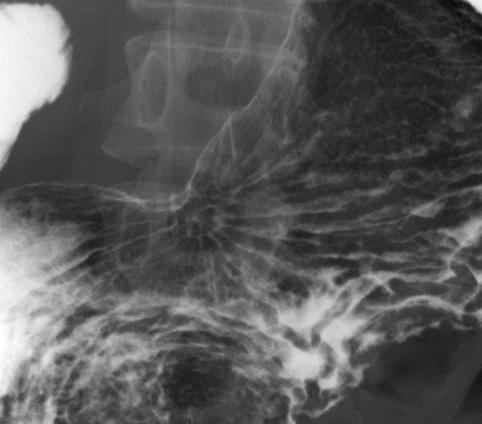

疾患(病理主体)の分類悪性上皮性腫瘍/腺癌

部位(臓器別)胃(部位)/胃角

検査方法X-P

腫瘍の肉眼分類0型(表在型)/IIc型(IIc)

病変の最大径(ミリ)35〜40

腫瘍の深達度m